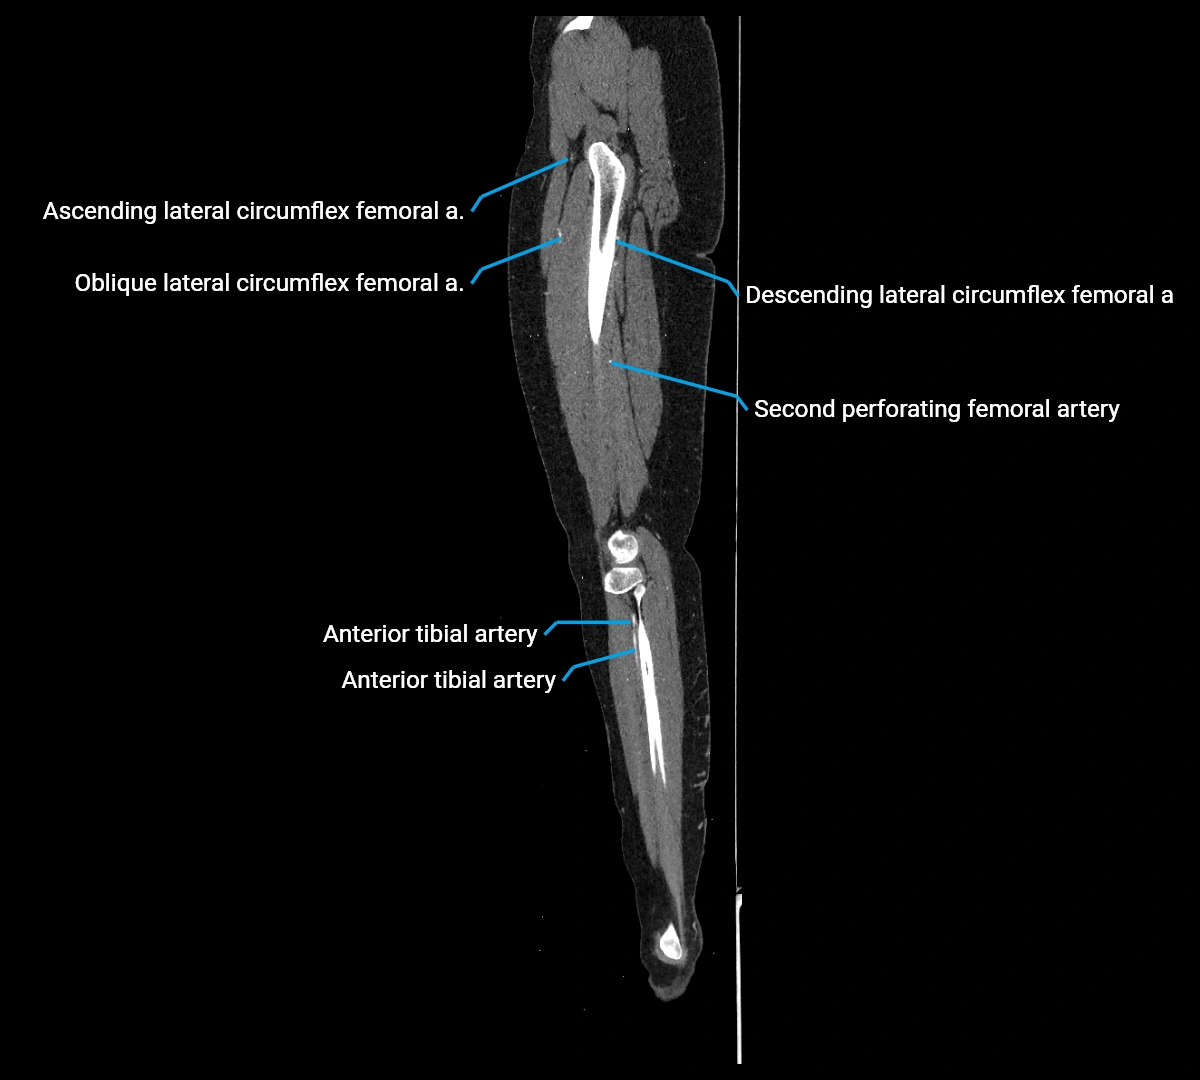

Contrast-enhanced CT (CTA):

• Gold standard for abdominal aortic imaging

• Provides excellent detail of lumen, wall, aneurysm, thrombus, and branch vessels

• Multiplanar and 3D reconstructions help in aneurysm measurement, stent graft planning, and dissection evaluation

• Detects acute rupture, traumatic injury, or occlusion with high sensitivity